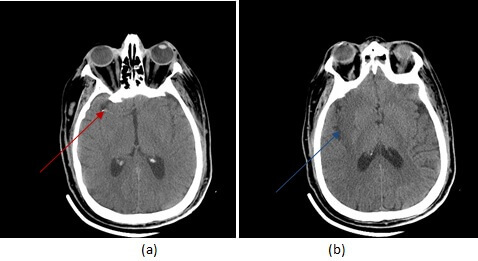

Diagnosis: Acute embolic non hemorrhagic right middle cerebral artery infarct on CT

Figure 1: (a,red arrow) axial non contrast CT demonstrates a hyperdense middle cerebral artery. There is loss of grey white differentiation involving the insular cortex and right basal ganglia (b,blue arrow).

CT is the initial imaging modality performed in the code stroke protocol. It is done primarily to exclude a hemorrhagic infarct, an absolute contraindication to the administration of TPA. However CT can also suggest the presence of a non hemorrhagic infarct with a sensitivity of approximately 70% – blurring of the junction between grey and white matter, especially in the insula is an early and often subtle sign of a non hemorrhagic infarct. A hyperdense MCA reflecting the increased attenuation of an clot within the vessel , is a specific sign for an embolic infarct.